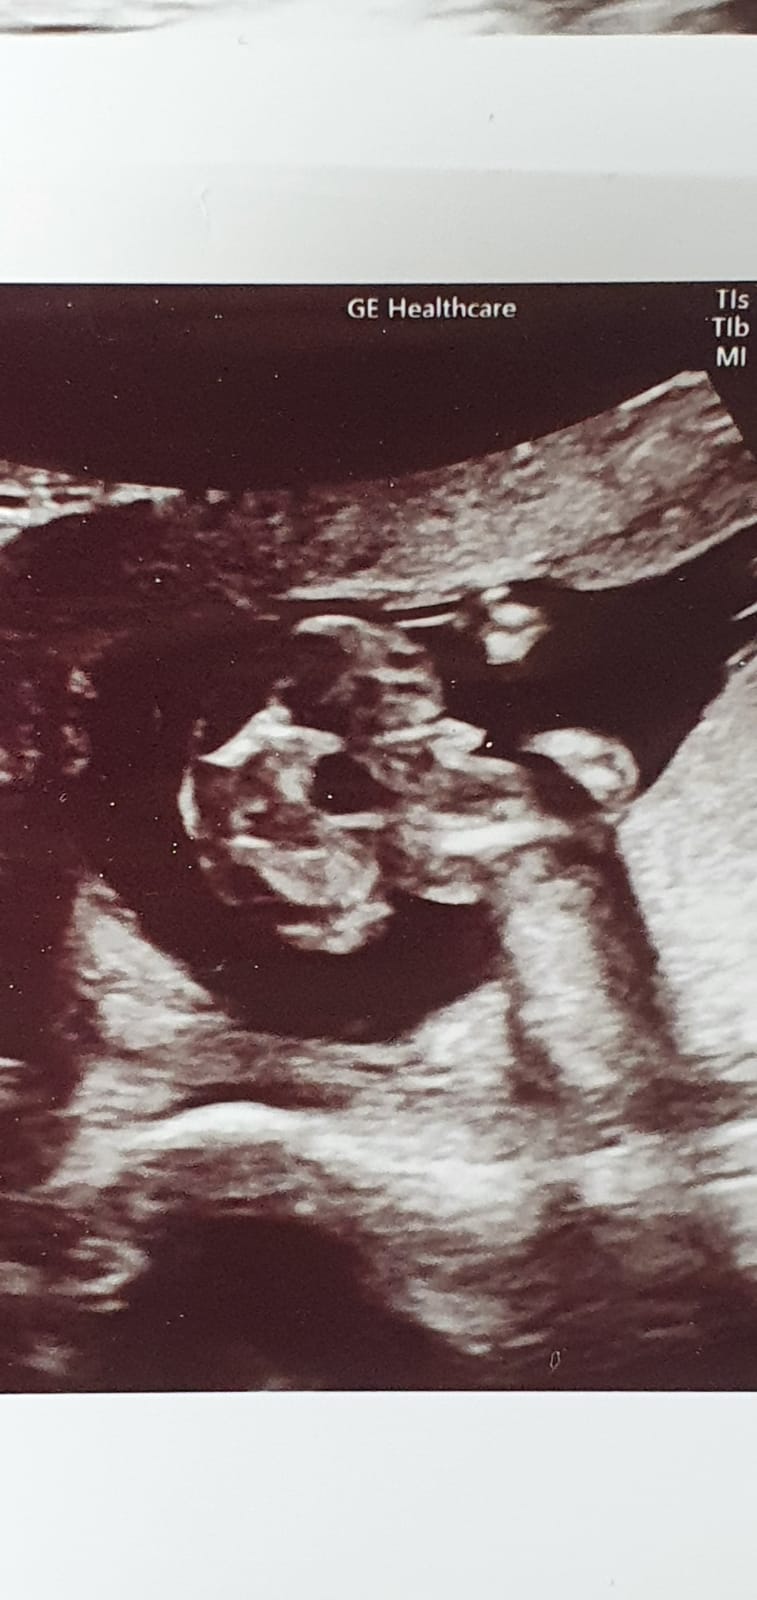

Hey dziewczyny .USG 12 tydzień ciąży.Widzicie tu chłopca czy dziewczynkę ? Zerknijcie proszę ...

Załączniki

• 115804223_339958607398878_5640781852298220012_n.jpg

115804223_339958607398878_5640781852298220012_n.jpg

162,2 KB · Wyświetleń: 368